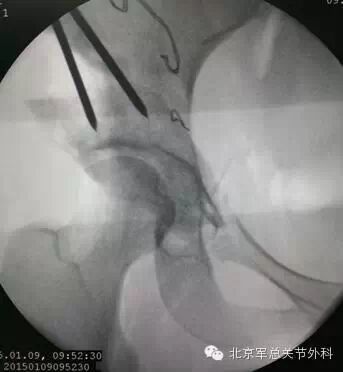

术中右髋臼周围截骨内固定透视影像。术中探查关节囊发现存在盂唇损伤、囊肿形成,行盂唇成型清理。